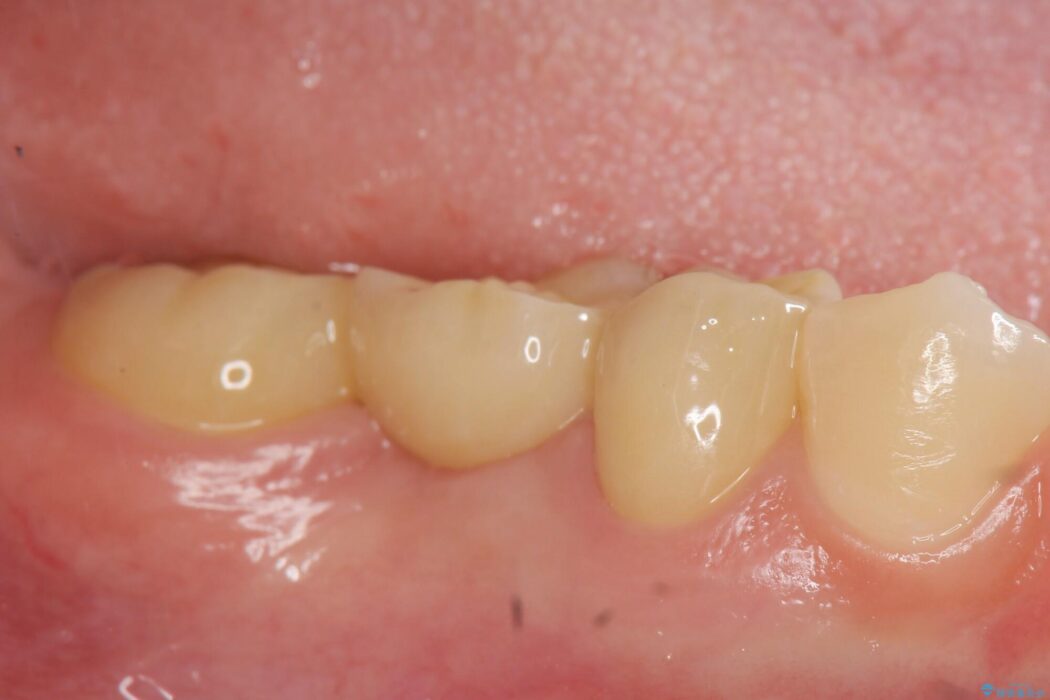

治療後について

欠損した部分が補綴され、普通に噛めるようになったと喜んでいただけました。

本症例では、健康な歯を可及的に守るため神経の処置を避けた上で部分矯正を併用して行うことにより、安全に補綴治療(ブリッジ)ができました。